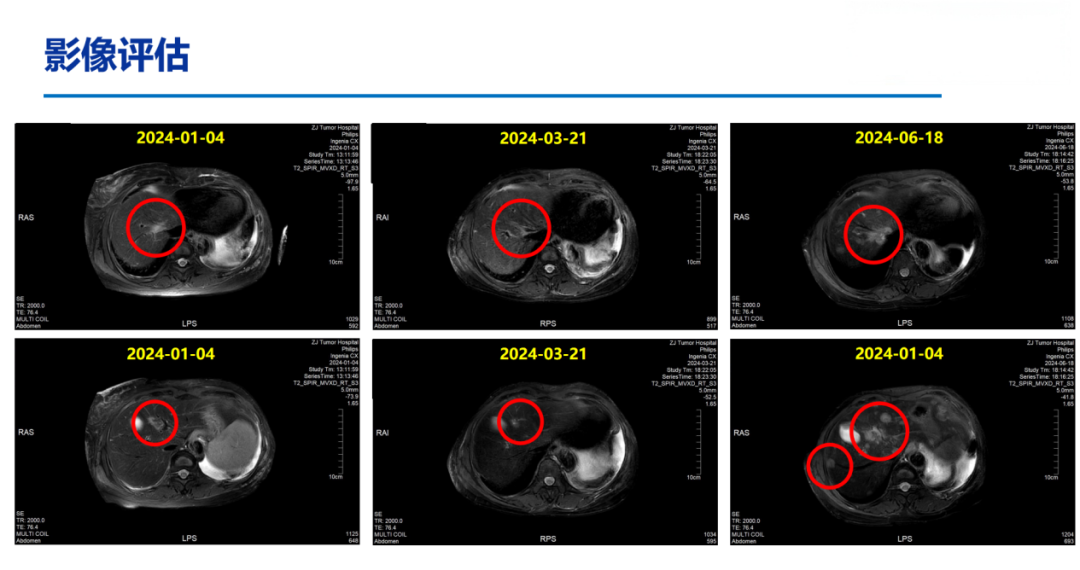

2024-01-05开始予氟维司群+达尔西利内分泌治疗维持。

2024-06-18上腹部MR:乳腺癌肝转移化疗后复查,对照2024.03.21MR:肝多发转移瘤,较前增多、增大。部分胸椎异常信号,考虑转移,较前相仿。

一线PFS:13月。

DB-04研究结果显示,在总人群中,T-DXd组的中位总生存期较化疗组显著延长;基于该研究结果,国内外多项权威指南已一致推荐T-DXd作为HER2低表达晚期乳腺癌的标准治疗方案,尤其适用于既往接受过治疗的患者。基于DB-04的研究数据、国内外指南推荐及其可及性,患者于2024-07-08至2025-02-25予11周期“德曲妥珠单抗300mg,q3w”治疗,2周期后PR。

患者于2010年5月行左侧乳腺癌根治术,术后接受辅助化疗及他莫昔芬内分泌治疗,疾病稳定长达10年。2020年出现胸壁及淋巴结转移,后历经多线治疗,包括来曲唑治疗、化疗及CDK4/6抑制剂维持,疾病仍持续进展。基于DB-04研究的优异数据,患者于2024年7月启动二线T-DXd单药治疗,2周期后即达PR,显示出T-DXd在HR+/HER2低表达人群中的高效性。

本病例中的患者为HR+/HER2低表达晚期乳腺癌,既往经内分泌治疗、化疗及CDK4/6抑制剂治疗后出现疾病进展,符合DB-04研究患者的入组条件且2024年T-DXd已经在我国获批HER2低表达领域的适应症,并实现药物可及。本例患者在接受T-DXd治疗2周期后即达PR,目前PFS已超过20个月且仍在持续接受治疗,这一案例进一步支持了T-DXd在HER2低表达晚期乳腺癌中的应用。